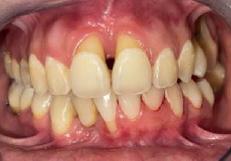

Lâexamen exobuccal Ă©tait sans particularitĂ©s. Lâexamen endobuccal a objectivĂ© une inflammation marginale modĂ©rĂ©e Ă sĂ©vĂšre gĂ©nĂ©ralisĂ©e avec un indice dâOleary Ă 68%, un indice gingival (BoP = Bleeding on Probing) Ă 76%, et un trama occlusal sur 42 (Figure 1). Le bilan parodontal montre des sites avec une profondeur de sondage (PS) de 12mm, et plus de 50% des dents prĂ©sentant une perte dâattache â„ 5mm. Le bilan radiographique a montrĂ© des pertes osseuses terminales, avec un rapport perte osseuse/Ăąge Ă 4,5 (Figure 1)

par quadrant (3) combinĂ©e Ă une antibiothĂ©rapie (3,4). Une chirurgie avec lambeau dâaccĂšs selon la technique du lambeau avec incision intrasulculaire (open flap) a Ă©tĂ© rĂ©alisĂ©e sur la 46. Une thĂ©rapie parodontale de soutien associĂ©e Ă une phase correctrice a Ă©tĂ© mise en place aprĂšs la thĂ©rapie parodontale active (5). La rĂ©habilitation orale a consistĂ© dans un premier temps Ă rĂ©aliser une correction orthodontique (Figure 2) ; et dans un second temps la conception dâune Ă©pithĂšse gingivale (Figure 3)

AprĂšs 6 mois, pas de profondeurs de poches â„ 6mm, avec un indice de plaque Ă 9% et un indice gingival < 10%. La thĂ©rapeutique non chirurgicale a permis un gain dâattache

stable qui sâest traduit par une diminution des profondeurs de sondage en regard de la 11, 21, et 36 dont le pronostic Ă©tait dĂ©favorable, mais aussi lâapparition dâimportantes rĂ©cessions postthĂ©rapeutique (Figure 4). La chirurgie avec lambeau dâaccĂšs a permis Ă©galement dâamĂ©liorer le niveau osseux de la 46. Le pronostic gĂ©nĂ©ral Ă long terme de la patiente a Ă©tĂ© amĂ©liorĂ©.

La rĂ©cession post-thĂ©rapeutique est une observation commune aprĂšs une instrumentation non chirurgicale, particuliĂšrement au niveau des poches profondes et/ou dâun phĂ©notype gingival fin. Notre patiente prĂ©sentait une RT3 sur les incisives centrales rendant son sourire inesthĂ©tique (trou noir). Les restaurations dentaires directes et indirectes et/ou Ă©pithĂšses pouvant ĂȘtre envisagĂ©es (5) ; nous avons optĂ© pour une solution moins invasive en rĂ©alisant une Ă©pithĂšse gingivale. Peu coĂ»teuse et pratique, elle a permis dâoptimiser le rĂ©sultat esthĂ©tique et fonctionnel dans un contexte socio-Ă©conomique limitĂ©.